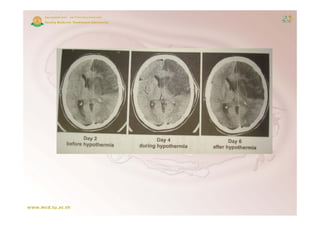

A case scenario

69 y/o woman presented to an outside

hospital with sudden onset of right sided

h    it l ith dd           t f i ht id d

weakness and speech impairment. She

arrived at the OSH at 20 minutes after

onset. CT brain was negative. TPA was

CT-brain

started at 90 minutes after the onset

before she was transferred to SLUH

SLUH.

A case scenario (cont )

(cont.)

She

Sh was alert and awake, b t aphasic.

l t d       k but h i

NIHSS was 8 with:

LOCb 2,

partial hemianopia

hemianopia,

right arm drifting,

some effort against gravity on right leg

leg,

partial sensory loss on the left side

moderate aphasia.

aphasia

Without ith i t b ti

With t either intubation or sedation,

d ti

therapeutic hypothermia with

endovascular cooling technique was

started at 5 hours after onset. Target core

temperature of 33oC was reached within 3

hrs. Shivering was under control with

combination of surface warming and

meperidine p

p         plus buspirone. Gradual

p

rewarming was applied after target

temperature was maintained for 24 hrs.